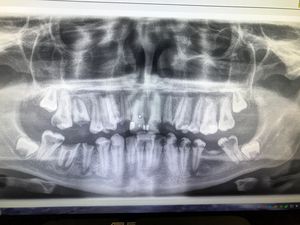

17 year old cane in with #3 and #30 hurting. What would you say to this kid and the parent? What would your treatment plan be?